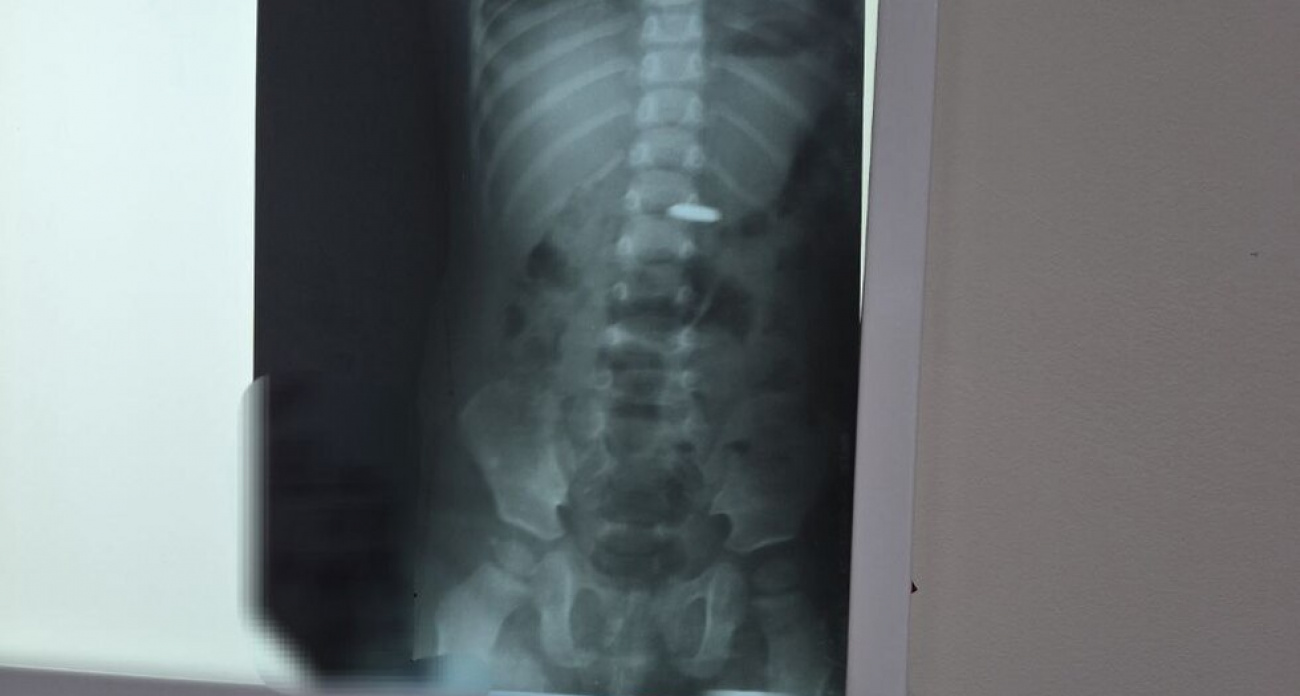

Врачи Балаковской городской клинической больницы успешно оказали помощь годовалому ребенку, который проглотил батарейку. Информацию об этом происшествии медицинское учреждение опубликовало в своем официальном Telegram-канале.

"Попадая внутрь, батарейка вызывает не просто ожог слизистой, но и глубокие поражения тканей, интоксикацию. Разгерметизация с утечкой электролита возможна уже через 2,5 часа, независимо от того, заряжена батарейка или нет", - сообщается в посте медучреждения.

После того как рентгенологическое исследование подтверждает наличие батарейки в пищеводе или желудке, ее оперативно извлекают при помощи эндоскопа. Тем не менее, если батарейка имеет большой диаметр, она может застрять в привратнике желудка (месте соединения желудка с кишечником) или зафиксироваться в кишечнике. В подобных ситуациях может потребоваться хирургическое вмешательство.